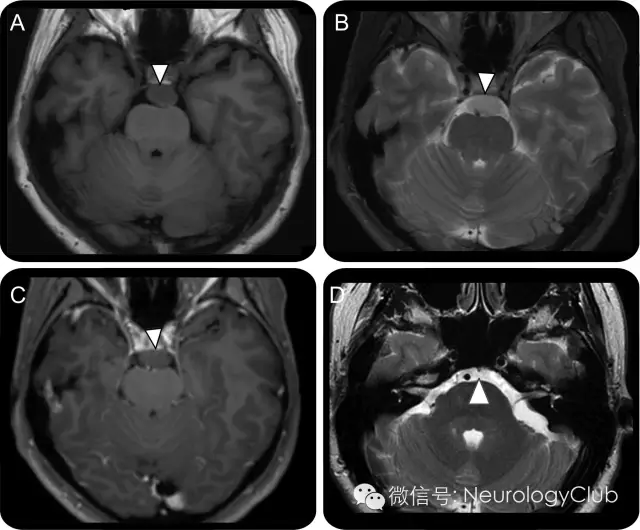

46岁女性,表现为慢性头痛和面部麻木。临床查体无殊。头颅MRI提示T1WI中等信号,T2WI高信号的斜坡肿块,无强化(图A-C)。脊索瘤,软骨肉瘤,表皮样囊肿,转移瘤等均有可能。但可见骨性蒂状结构,证实肿块为颅内脊索瘤(图D)。

(3T磁共振上可见一卵圆形,边界清楚的斜坡区肿块,T1WI上为中等信号[A],T2WI上为稍高信号[B],注射对比剂后无明显强化[C];可见骨性蒂状结构从斜坡背侧发出延伸至肿块,可明确为颅内脊索瘤[D])

最终诊断

颅内脊索瘤

影像学上认识颅内脊索瘤(一种良性的脊索残留物)可避免不必要的活检。骨性蒂状结构的存在有诊断意义,其在CT和MRI上均可见到。多数患者没有症状,但也可出现头痛,视觉障碍,步态不稳和感觉异常。